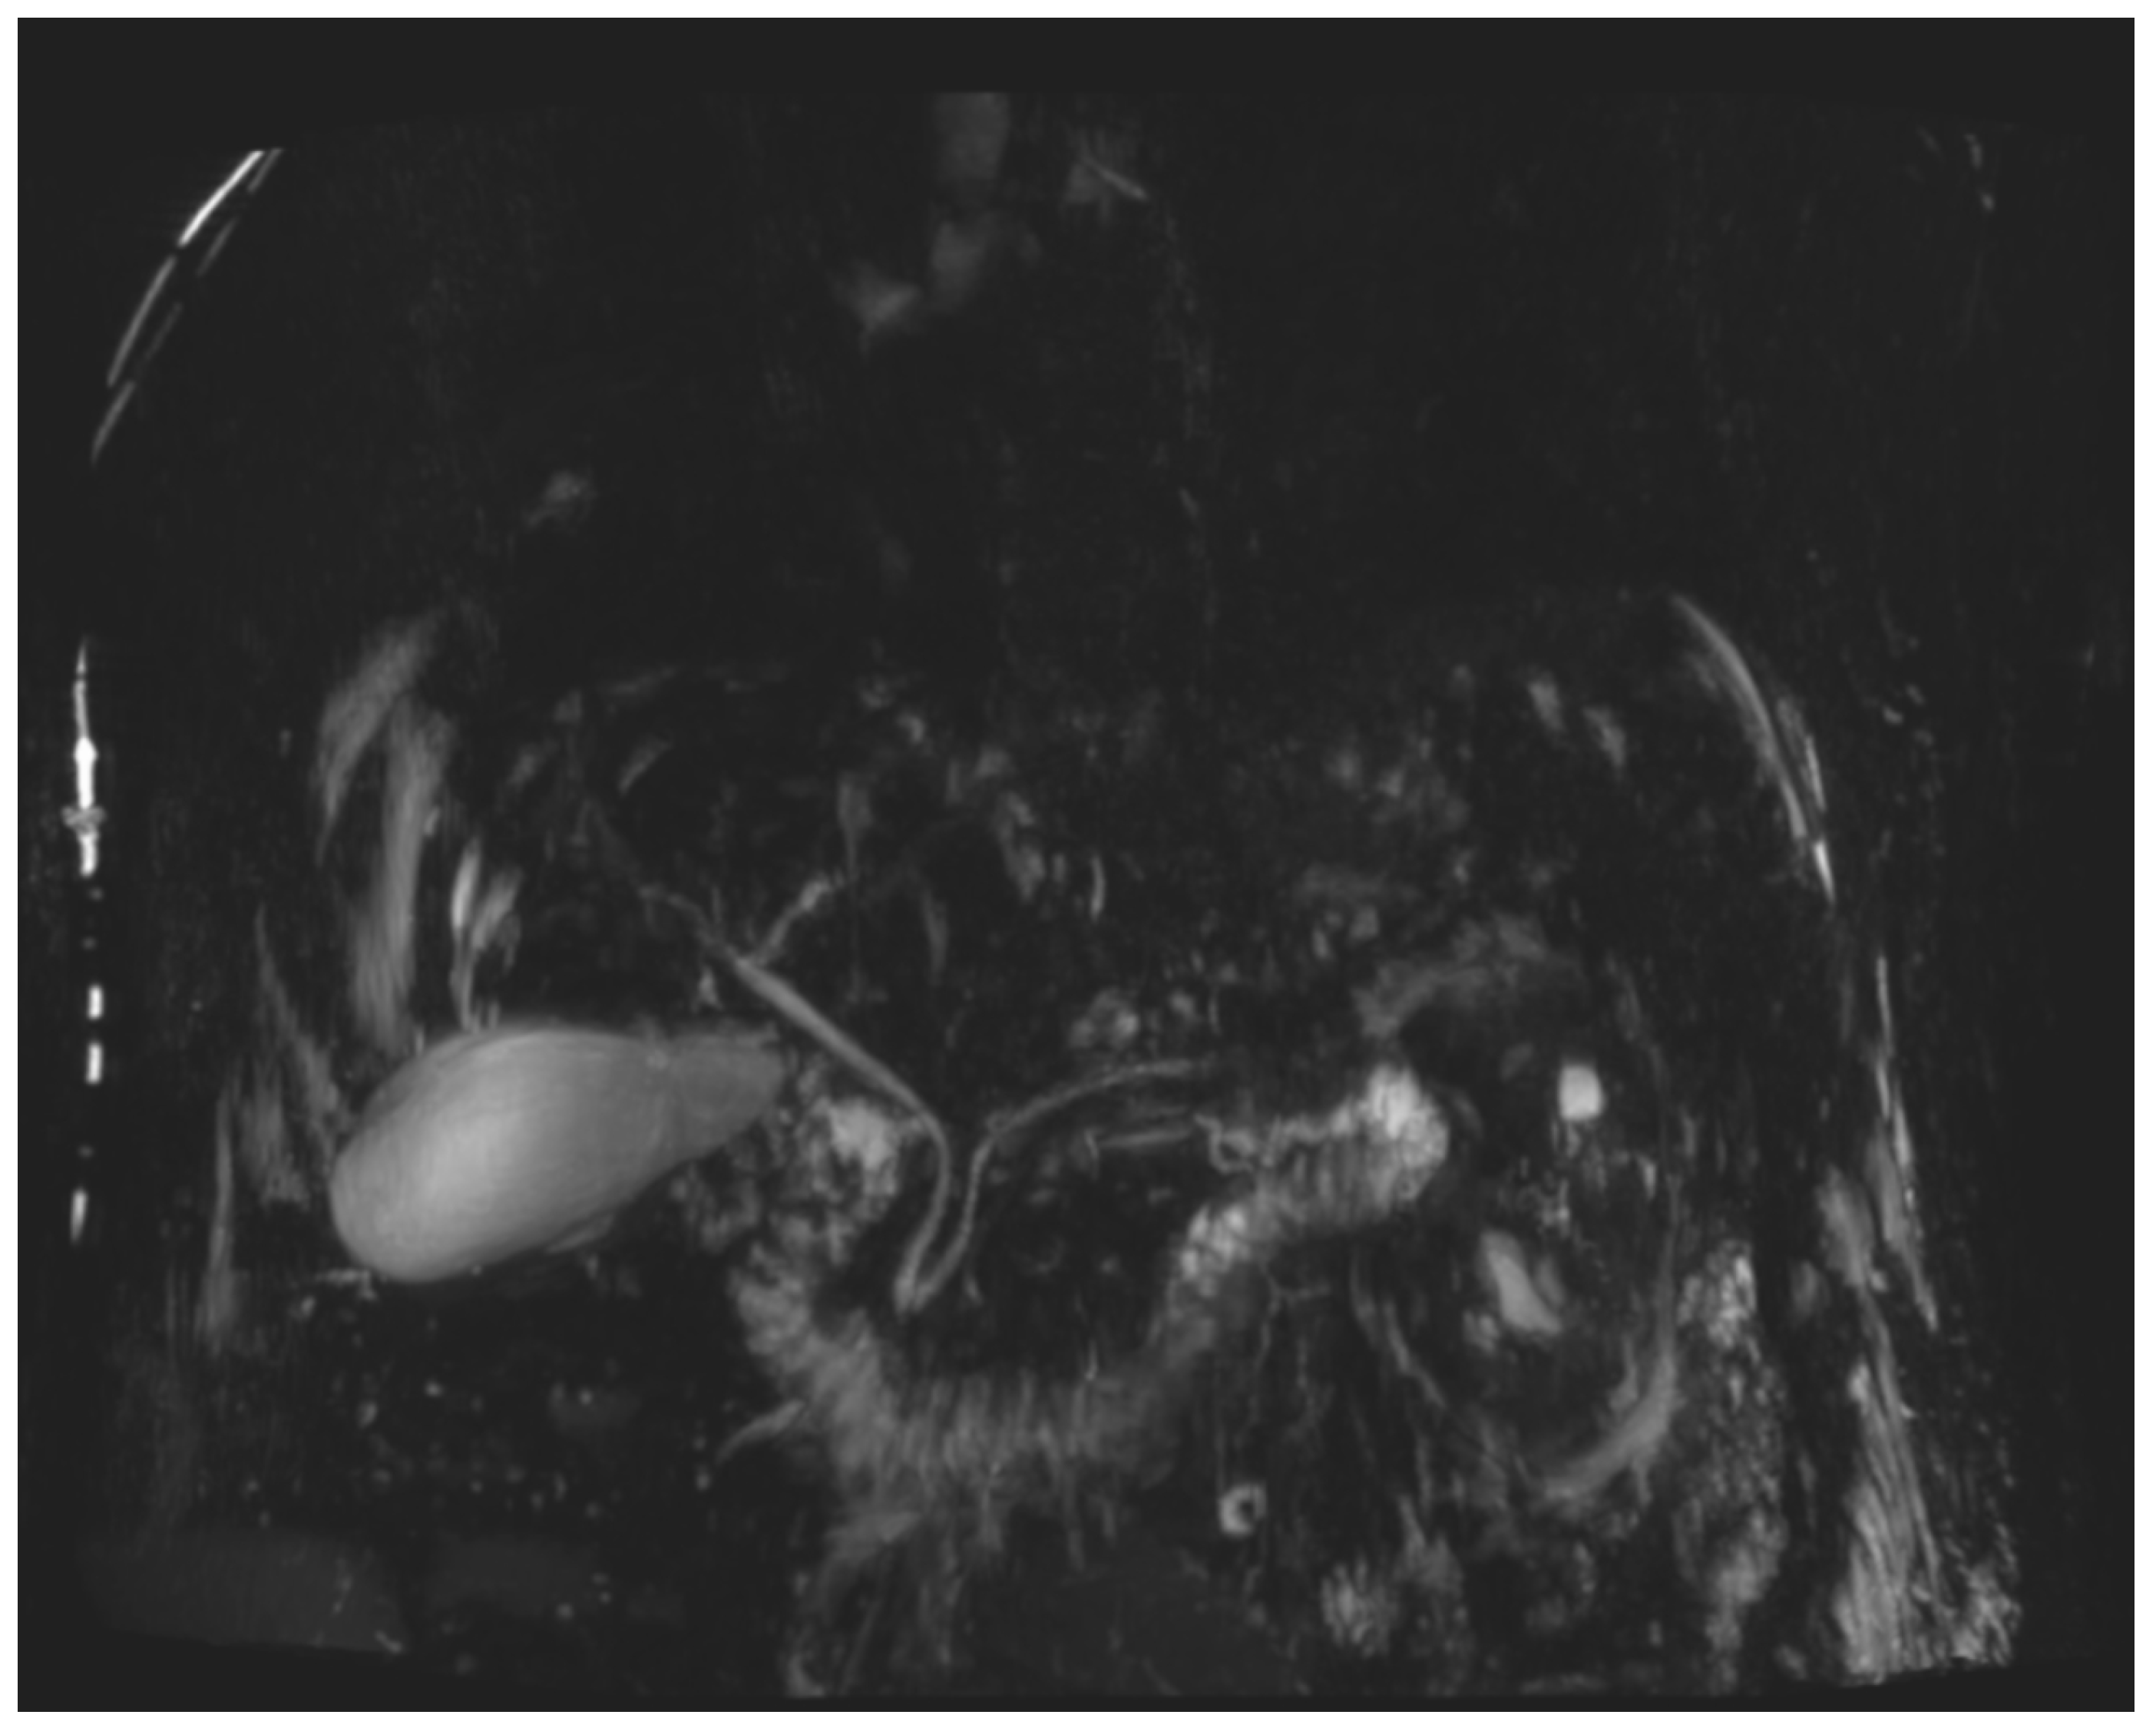

During the first days of mycophenolate therapy, a transient biochemical flare was observed (20 August 2025), with total bilirubin peaking at 4.7 mg/dL (direct 3.7 mg/dL), ALP 214 U/L, and GGT 1195 U/L. A magnetic resonance cholangiopancreatography performed the same day showed normal intrahepatic and extrahepatic bile ducts with no obstruction (Figure 3 and Figure 4). Over the following week, a partial biochemical improvement occurred (27 August 2025): ALT 222 U/L, AST 96 U/L, ALP 481 U/L, GGT 1758 U/L, total bilirubin 1.9 mg/dL.

Figure 3. Three-dimensional MR cholangiopancreatography (3D-MRCP). The intrahepatic and extrahepatic bile ducts appear normal in caliber and course, with no evidence of stenosis or dilatation.